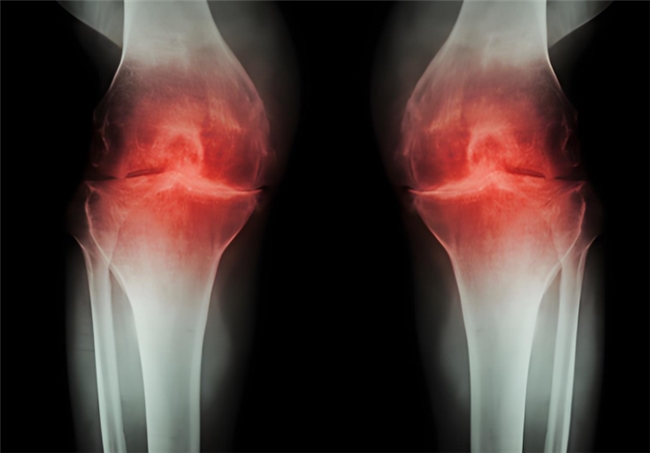

骨關(guān)節(jié)炎作為常見(jiàn)的關(guān)節(jié)退行性疾病,困擾著眾多中老年人乃至長(zhǎng)期勞損的人群?;颊卟粌H會(huì)頻繁遭遇關(guān)節(jié)疼痛、腫脹、僵硬等不適,隨著病情發(fā)展,還可能出現(xiàn)活動(dòng)受限、關(guān)節(jié)變形,進(jìn)而影響走路、上下樓等日常行為,讓生活質(zhì)量大打折扣。更令人擔(dān)憂(yōu)的是,骨關(guān)節(jié)炎的病程一旦進(jìn)入中晚期,治療難度和痛苦都會(huì)明顯增加。因此,及早干預(yù)至關(guān)重要。而氨基葡萄糖就是臨床常用的治療藥物之一,但它還有鹽酸和硫酸氨基葡萄糖之分,到底鹽酸和硫酸氨基葡萄糖的作用與功效有什么不同?骨關(guān)節(jié)炎患者如何選擇呢?

鹽酸和硫酸氨基葡萄糖膠囊都是氨基葡萄糖類(lèi)藥物,能為關(guān)節(jié)軟骨提供合成原料,在促進(jìn)軟骨基質(zhì)的修復(fù)與再生的基礎(chǔ)上,補(bǔ)充關(guān)節(jié)滑液以減少摩擦,同時(shí)通過(guò)抑制關(guān)節(jié)腔內(nèi)的炎癥因子,從多個(gè)方面幫助延緩骨關(guān)節(jié)炎的進(jìn)展[1],但它們?cè)谂R床療效上卻存在一定差異。

根據(jù)國(guó)際醫(yī)學(xué)四大期刊之一《美國(guó)醫(yī)學(xué)會(huì)雜志》上發(fā)布的一項(xiàng)研究表明,硫酸氨基葡萄糖在緩解膝骨關(guān)節(jié)炎疼痛、改善關(guān)節(jié)活動(dòng)功能方面,效果優(yōu)于鹽酸氨糖等33種骨關(guān)節(jié)炎常用藥[2]。還有相關(guān)研究顯示,硫酸氨基葡萄糖不僅能延緩關(guān)節(jié)間隙變窄,還能從根源改善關(guān)節(jié)結(jié)構(gòu)、減緩磨損。而鹽酸氨基葡萄糖在這一關(guān)鍵指標(biāo)上的效果尚未明確。因此,在關(guān)節(jié)保護(hù)的“確切性”上,硫酸氨基葡萄糖顯然更具優(yōu)勢(shì)。